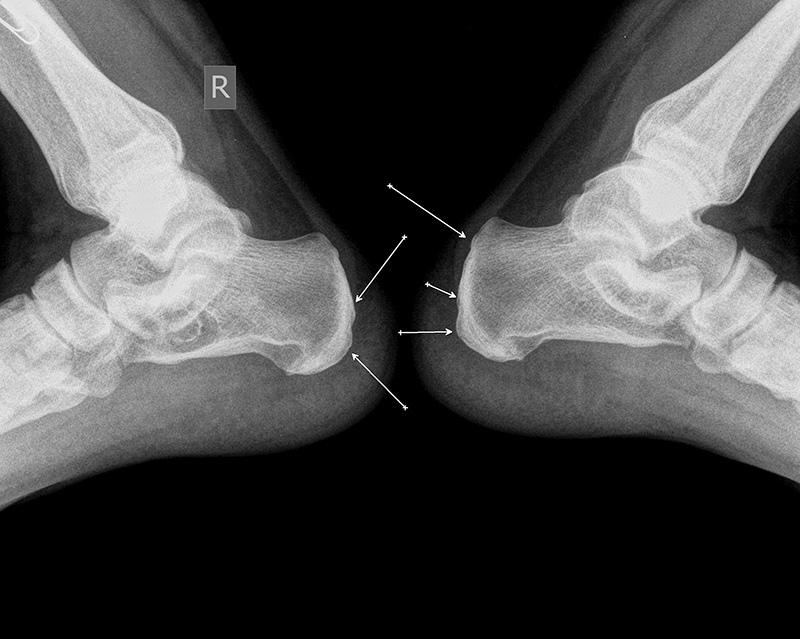

10. Рентгенография обеих стоп-контуры пяточных костей четкие, ровные, по подошвенным поверхностям с обеих сторон - мелкие остеофиты, больше справа, деструктивных изменений не выявлено.

11. На рентгенограмме правого голеностопного сустава в 2х проекциях -консолидированный перелом в области латеральной лодыжки.